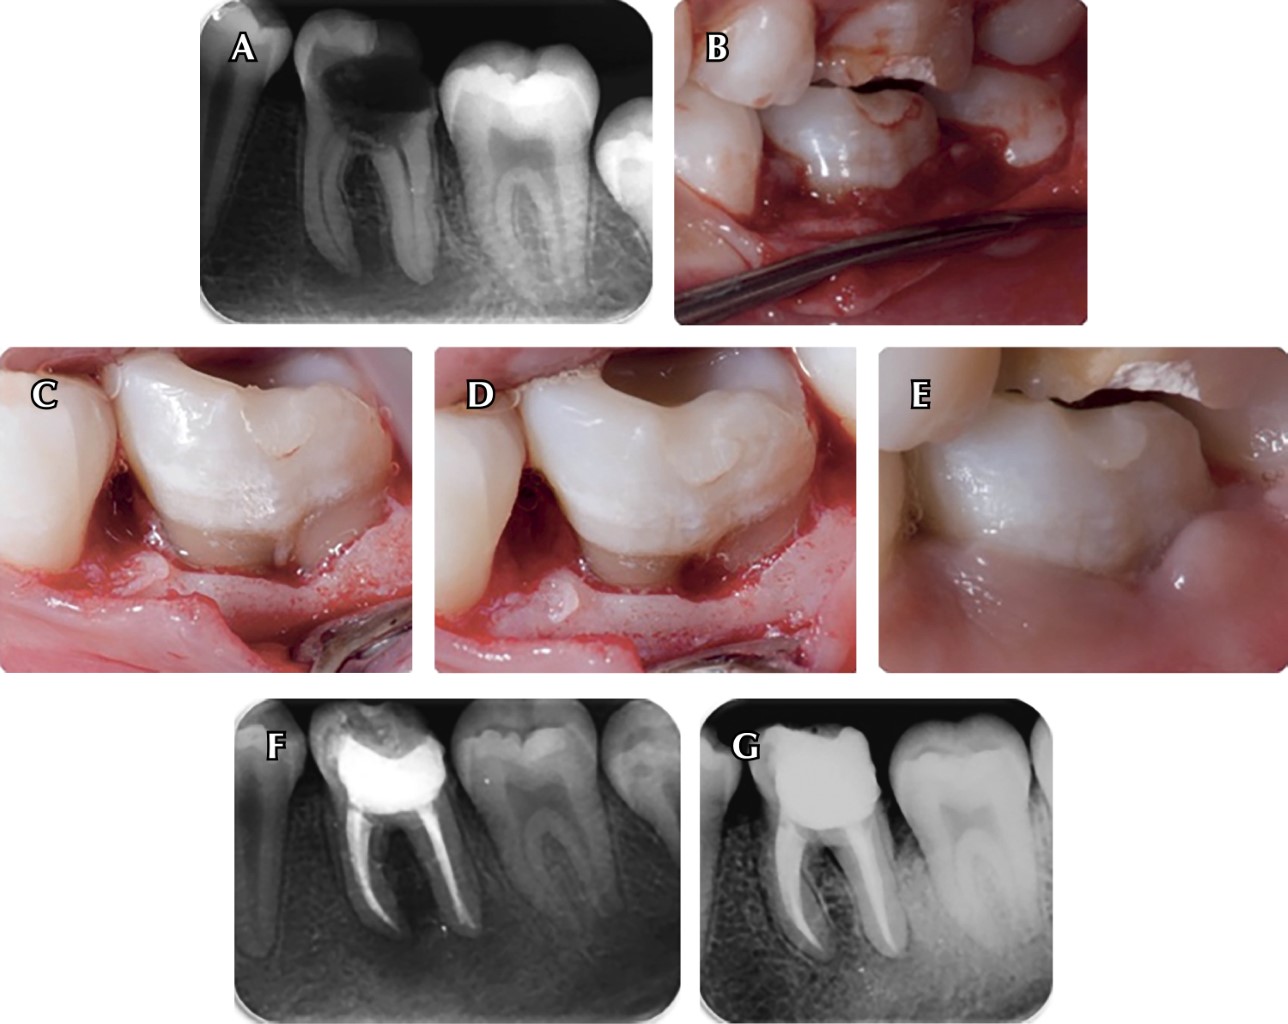

Para este procedimiento es necesario realizar una elevación de colgajo para tener acceso al área interradicular, remoción del tejido inflamatorio por medio de un raspado y alisado radicular y la posterior odontoplastia y osteoplastia para reducir el componente horizontal del defecto y aumentar el tamaño de la entrada a la furca. Es necesario que la sutura quede a nivel de la cresta alveolar, cubriendo la entrada a la bifurcación. La cicatrización en esta zona debe ser "como una papila"48 (Figura 2).

Resección radicular

Los términos "amputación radicular" y "hemisección" se conocen colectivamente como "resección radicular".51 Es necesario realizar una distinción entre los procedimientos de resección de la raíz (RR) y resección de la corona (CR). El primero consiste en la amputación de la raíz o cualquier RR a nivel de la unión amelocementaria sin remover partes de la corona. Mientras que la resección de la corona incluye la hemisección, trisección y premolarización (bicuspidación). Asimismo, ésta abarca todos los tratamientos en los que la separación atraviesa la bifurcación y la corona de un diente multirradicular, de tal manera que se puede extraer una raíz y su porción asociada de la corona (hemisección o trisección) (Figura 3) o se conservan todas las secciones de la raíz/corona (premolarización o bicuspidación).52